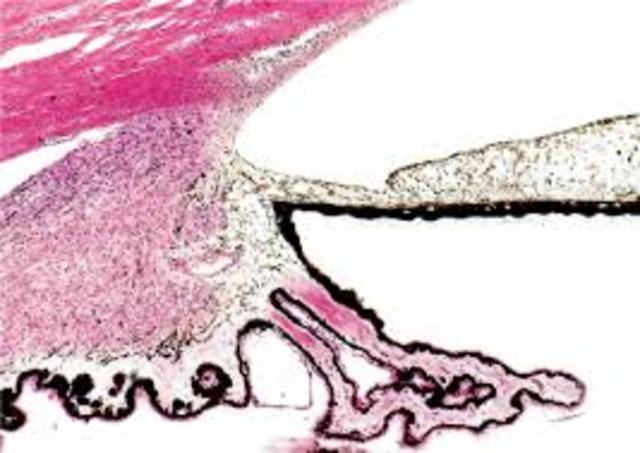

• Décima semana

Décima semana

La retina es más gruesa:conos y bastoncillos aparecen en la zona más externa, y la capa del manto la cubre, la parte más interna está formada por fibras que vienen de neuronas de capas vecinas que llegan hacia el conducto óptico, que vemos cubierto de fibras. La porción ciega de la retina formará el iris y zona ciliar, separadas de la retina óptica por la ora serrata. El mesodermo circundante se diferencia en capa interna: la membrana íridopupilar, y externa: la esclerótica y la córnea.